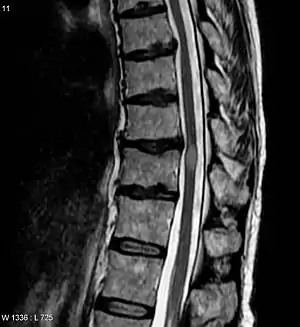

| Acute myelitis | intramedullary lesion > 3 contiguous segments, or spinal atrophy ≥ 3 contiguous segments |